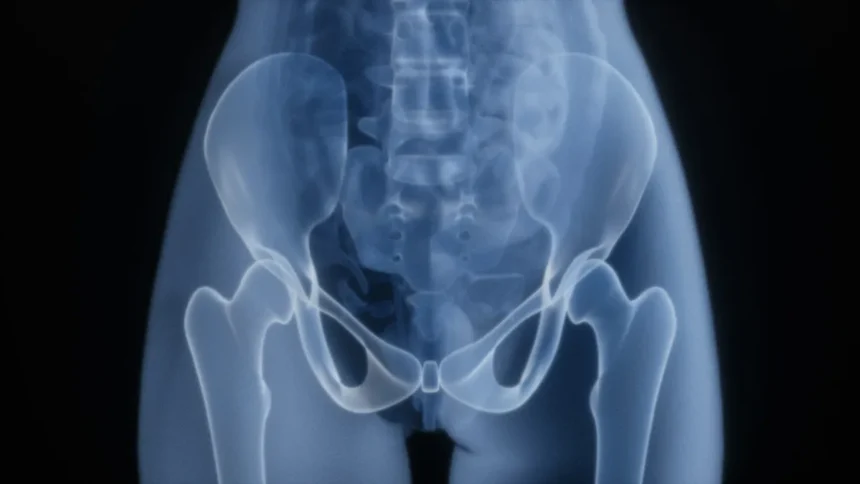

A csípőfájdalom hátterében számtalan ok állhat – magyarázza Dr. Németh Balázs ortopéd szakorvos. A leggyakoribbak között szerepel a kopásos ízületi gyulladás (artrózis), amely főként 50 év felett jelentkezik, de akár sportolóknál fiatalabb korban is kialakulhat. Emellett a csípőtáji izomhúzódás, íngyulladás, csonthártyagyulladás, porckorongsérv vagy az ún. piriformis szindróma is állhat a panaszok hátterében. „A pontos diagnózis felállítása kulcsfontosságú, mert teljesen más kezelést igényel például egy gyulladásos folyamat, mint egy strukturális elváltozás” – hangsúlyozza a szakember.